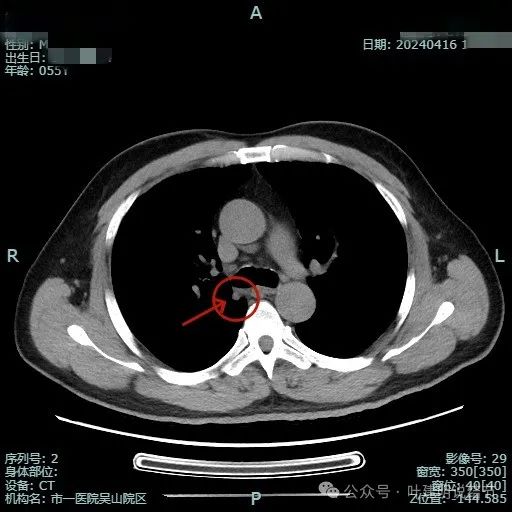

我们先来看2024年4月的病灶影像:

病灶出现,位于右上叶靠近肺门侧,此层显得像磨玻璃密度,轮廓较清。

其实应该实性密度的,前面层面应该是较为边缘部位的关系。病灶表面有点毛糙。

结节毛刺明显,而且是细毛刺。

有微血管走向病灶,结节与纵隔侧紧贴,但胸膜牵拉不明显。

有明显血管征,而且进入的血管是弯曲改变走行的。

表面不平显毛糙,有细毛刺。

此层显得病灶缺乏膨胀性,边缘较为平直。

边缘区较淡,也显得有点散。

病灶没有钙化。

纵隔窗可见。